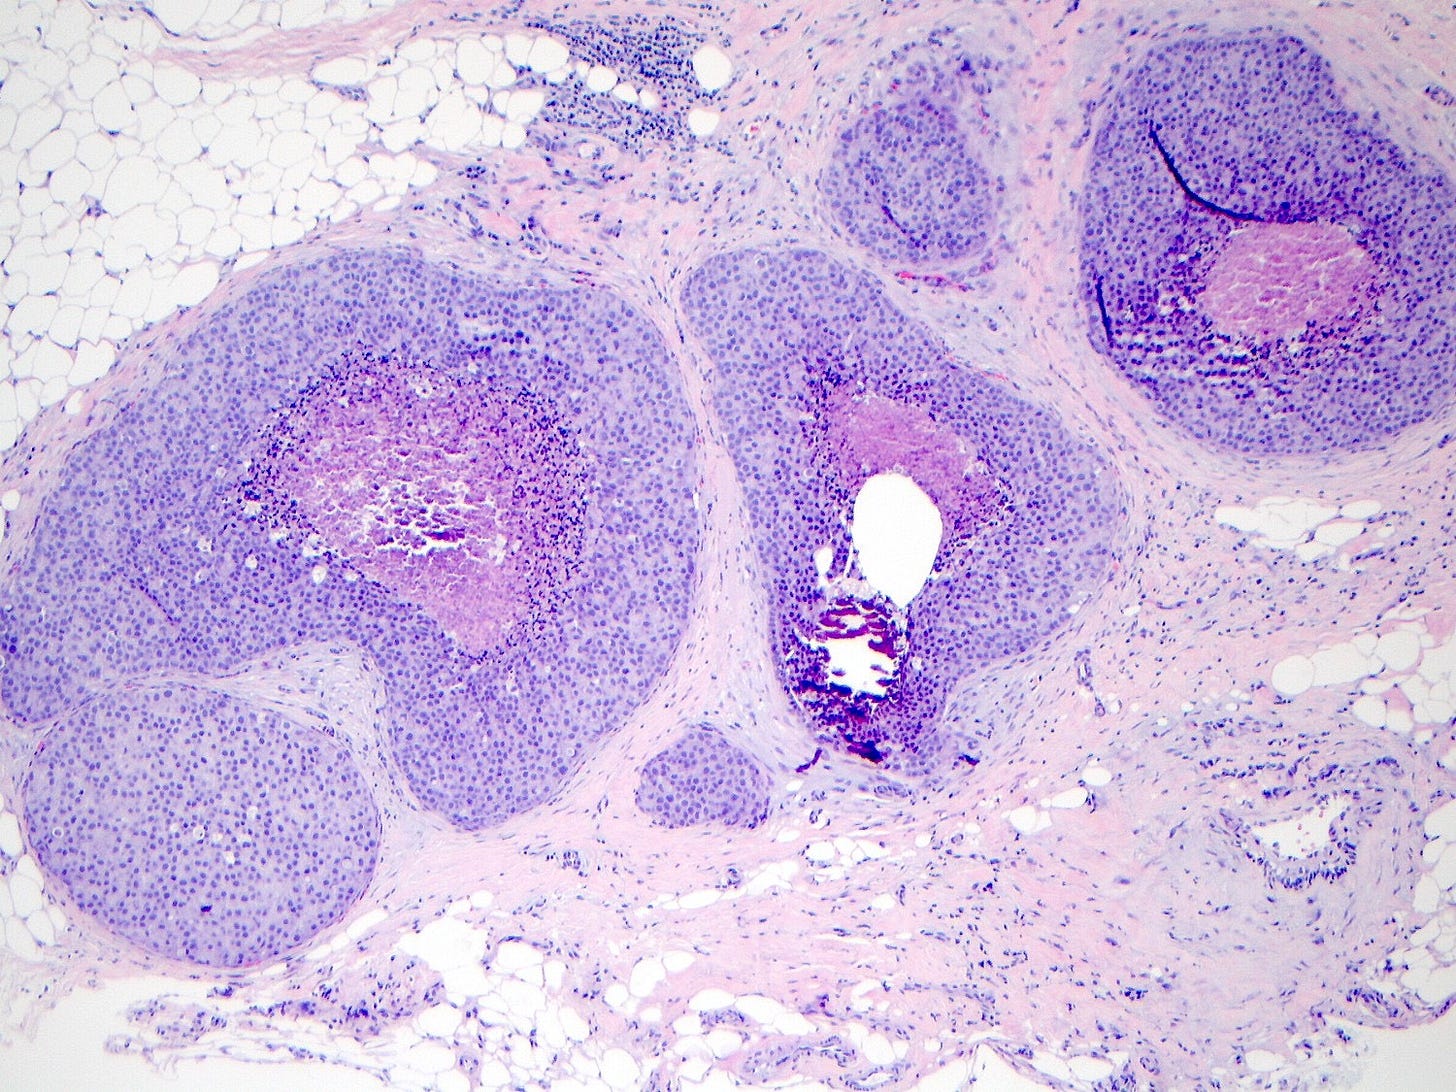

Classic LCIS - microscopic images

As shown below, LCIS is characterized by a lobulocentric proliferation of cells that expand lobular units. The LCIS cells are uniform, loosely cohesive and evenly spaced (“marbles in a bag”). They are slightly larger than normal breast epithelial cells, with indistinct cell borders and pale cytoplasm. Two types may coexist. Type A LCIS cells have small to slightly enlarged, uniform, round nuclei with inconspicuous nucleoli. Type B cells have larger nuclei, more abundant cytoplasm and more prominent nucleoli.

Classic LCIS is usually an incidental finding in a breast biopsy performed for other indications, including screening detected calcifications or mass producing lesions. The calcifications are frequently produced by columnar cell lesions, a low risk lesion. LCIS lesions are frequently found as multiple foci within the same (70%) or both breasts (20 - 60%).

LCIS is a risk factor for subsequent breast cancer: women with LCIS have a 7 - 10 fold increase in breast cancer risk, an absolute risk of 1 - 2% per year and a lifetime risk of 30 - 40%. The time from LCIS diagnosis to cancer ranges from 15 to 30 years.

Classic LCIS is typically treated conservatively with active surveillance and anti estrogens. Unlike DCIS, it is no longer considered a malignant condition. If diagnosed incidentally, excision is not recommended because the risk of finding invasive carcinoma on excision is very low (< 5%). Excision is recommended only if other high risk proliferative lesions are found or there is discordance between histology and imaging (i.e. the microscopic findings are different from what is expected from the imaging, suggesting the lesion was missed).